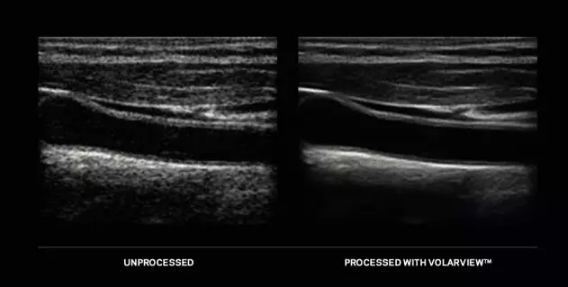

VolarView™ - 康泰瑞影全球领先的影像增强技术现在已经可以应用于手持超声市场。VolarViewTM可有效部署在手机和平板等各类手持设备上。随着手持设备可用性的增加,超声应用已超越传统范围,应用领域和用户变得更为广泛。康泰瑞影现已为全类别超声系统提供智能影像增强技术,以满足日益增加的照料病患的需求。